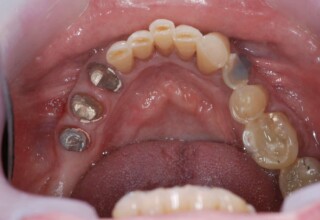

Εκτεταμένο Περιστατικό Ακίνητης Αποκατάστασης

Εκτεταμένη αποκατάσταση με στεφάνες(θήκες) σχεδόν σε όλα τα δόντια λόγω εκτεταμένων αποτριβών, παλαιών αποκαταστάσεων, οπισθίων απονευρώσεων και αισθητικών προβλημάτων. Ο ασθενής(60 ετών) παρουσίαζε έντονο βρυγμό (τρίξιμο δοντιών) που δεν είχε αντιμετωπίσει ποτέ, με αποτέλεσμα μεγάλες αποτριβές που απειλούσαν την ακεραιότητα των οπισθίων δοντιών. Οι ανασυστάσεις(σφραγίσματα) των δοντιών έγιναν κυρίως με συγκολλούμενα ρητινώδη υλικά και τρεις χυτούς άξονες ψευδοκολοβώματα. Τοποθετήθηκαν προσωρινές στεφάνες όπου εκτιμήθηκε το επιθυμητό μέγεθος, το σχήμα και η θέση των δοντιών πριν κατασκευαστούν οι τελικές μόνιμες στεφάνες.